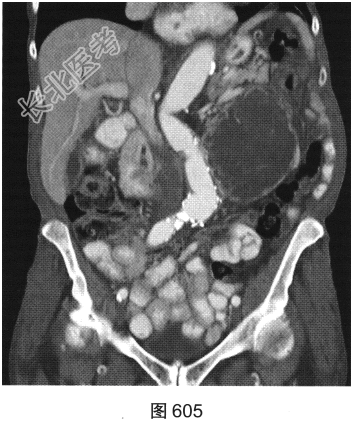

- [材料题] 患者女性,85岁,腹主动脉瘤破裂手术修复后,腹部疼痛。患者行腹部CT检查,见图603~图607。

- 简答题1、请对该病变CT影像表现进行描述。